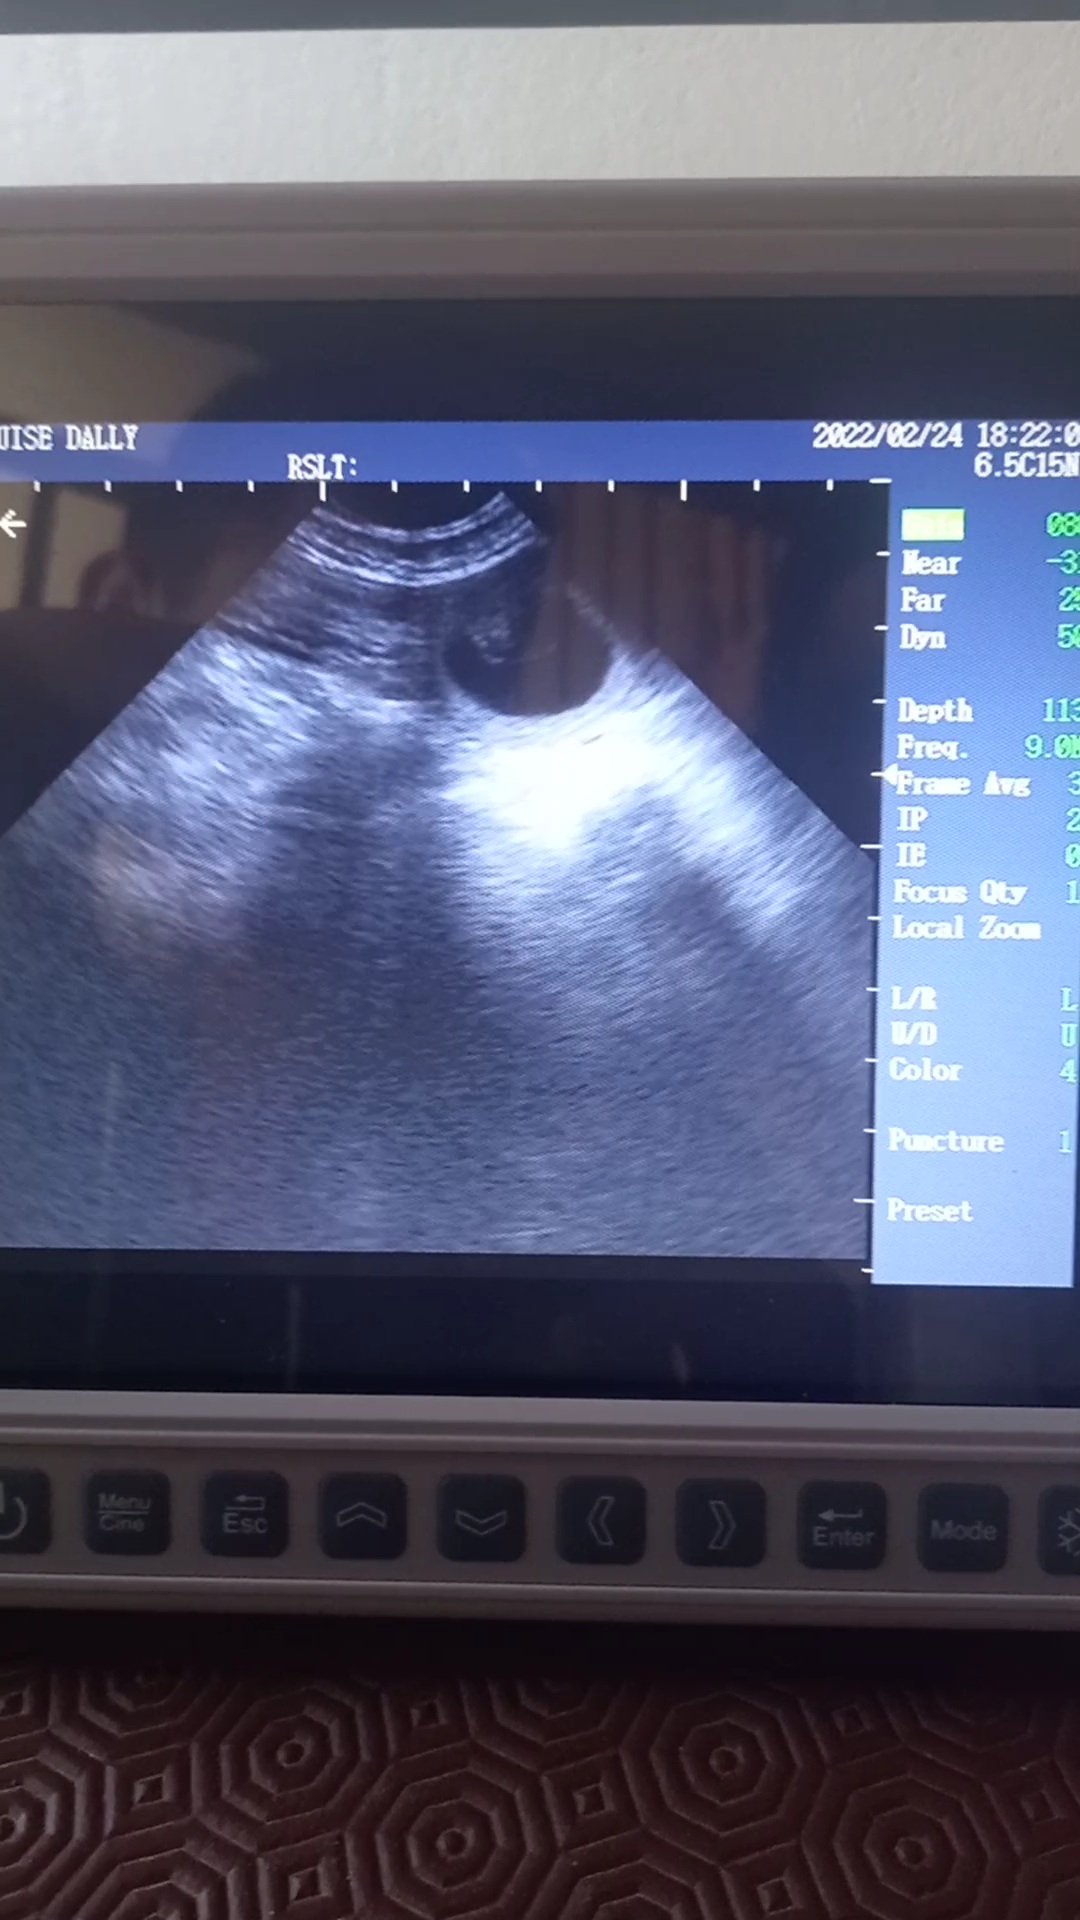

Beautiful scan of a 4yr old Labrador, confirmed multiple pups at 30days.